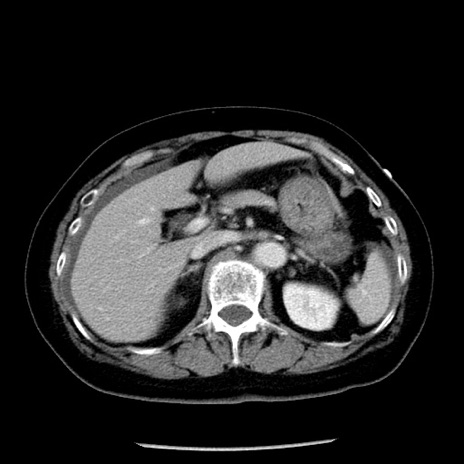

症例13(横断像)

【症例】70歳代女性

【主訴】腹痛、嘔吐

【現病歴】15時間程前(昨晩)より腹痛あり。今朝になっても症状の改善なく、嘔吐あり。腹痛も増悪あり、救急外来受診。

【既往歴】子宮癌全摘術後

【身体所見】意識清明、BP 121/72mmHg、P 74bpm、SpO2 100%(RA)、腹部:平坦・軟、腸雑音ほぼ聴取せず。下腹部・心窩部・臍左上に圧痛あり。反跳痛なし。

【データ】WBC 10600、CRP 0.15